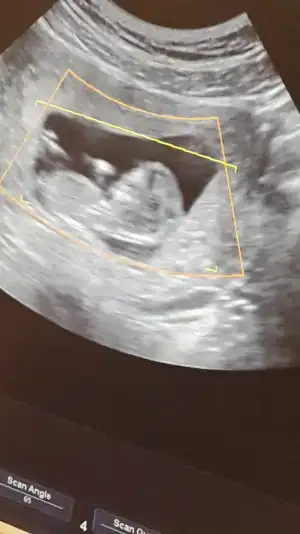

• 20150223_181758.webp

20150223_181758.webp

12,5 KB · Görüntüleme: 92

Selamm canlarim bizde 12haftadayiz ilk çocuğumuz çok merak ediyorum cinsiyetini bi annem kız diyo diğerleri erkek anladiklarindan dgl de tahmin yüzüm cok kızardı lekelendi sivilcelendi iştahsızlık var hep pek bisey yiyemiyom ama hayırlısı bakalım sizce kız mi bebisim erkek mi simdiden çok teşekkür ederim hepinize...